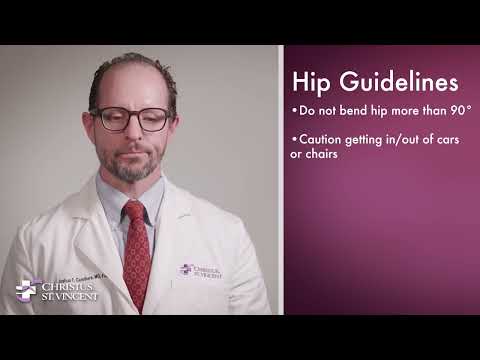

Hip

Bursitis, fractures, arthritis and dislocation all can cause major pain to the hip. CHRISTUS Health has several treatment options to relieve hip pain.

Hip Dislocation

The hip is one of the largest joints in your body and an important structure for maintaining proper balance and stability.

Learn More -

Hip Fractures

A CHRISTUS Health physician will help you improve quality of life, whether you need hip surgery or you need to strengthen your muscles around your joints through physical therapy.

Hip Replacement

If you suffer from restricted mobility in the hip you may be a candidate for hip replacement surgery.